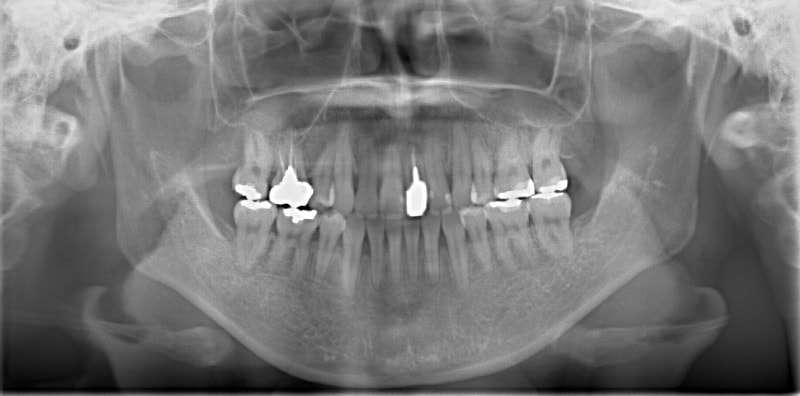

治療開始時

修復歯、補綴歯もあります。下顎8番が水平埋伏しています。

下顎8番は、両側抜歯済みです。